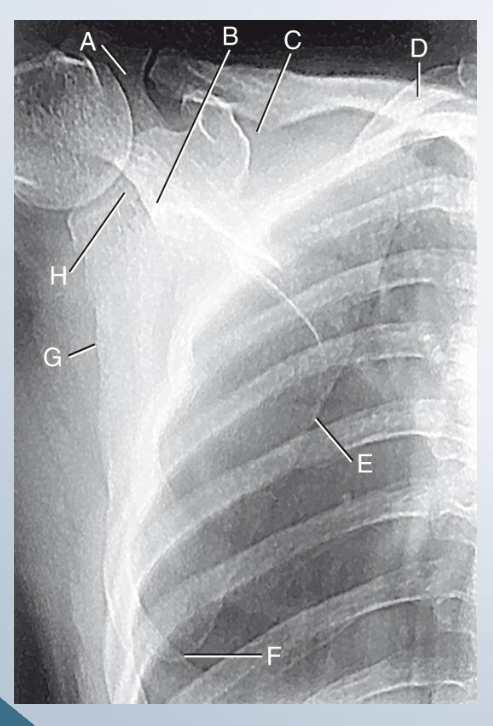

AP scapula

LABEL

A. Acromion

B. Neck of scapula

C. Suprascapular notch

D. Superior angle

E. Medial border

F. Inferior angle

G. Lateral border

H. Glenoid cavity